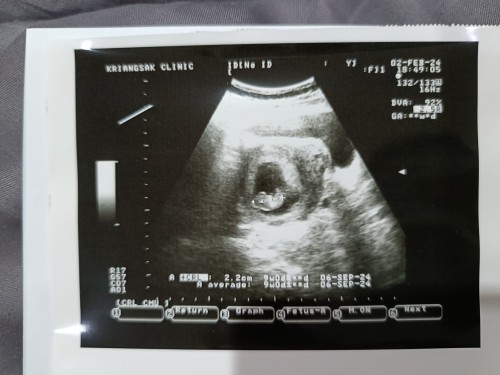

สวัสดีค่ะ ภาพแรกหนู9wเองคับ ภาพทที่2 หนู จะ18wแล้ว เห็นอวัยวะศรีษะและก็ขาหมดแล้วคับพี่ๆน้าๆ 👶🏻💗